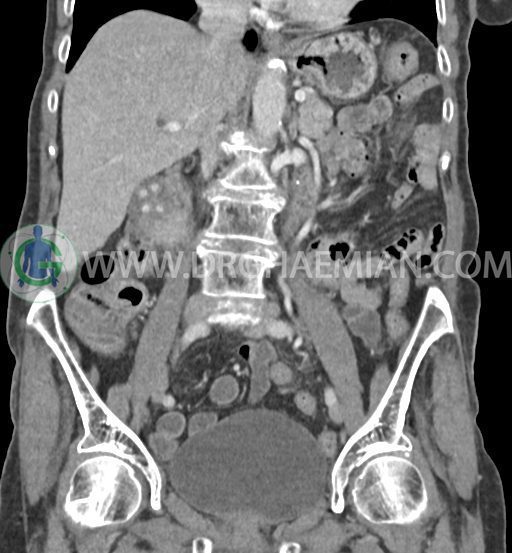

در سی تی اسکن اسپیرال شکم و لگن با و بدون کنتراست خوراکی و وریدی (مولتی دیدکتور 16 با مقاطع ظریف و بازسازی های ساژیتال و کرونال) :

تصویر توده اندکی هیپودنس (HU=40 ) به ابعاد 30x40mm در سگمان 4b کبد ، با حدود ناواضح با enhancement هتروژن و قابل توجه پس از تزریق کنتراست ( HU=70 )، با شواهد تهاجم به گردن کیسه صفرا

تصویر شبیه به توده به قطر 15mm بین خم کبدی کولون و سگمان 6 کبد و قطب تحتانی کلیه راست و به قطر 8mm در انتریور سکوم مطرح کننده توده های peritoneal

کیسه صفرای دیلاته حاوی اسلاژ و سنگ های فراوان به قطر 5mm تا 10mm مطرح کننده کولانژیوکارسینوما

دیلاتاسیون خفیف مجاری صفراوی داخل کبدی

کیست کورتیکال 40mm در قسمت تحتانی کلیه چپ

کلسیفیکاسیون دیواره آئورت و شریان های ایلیاک و